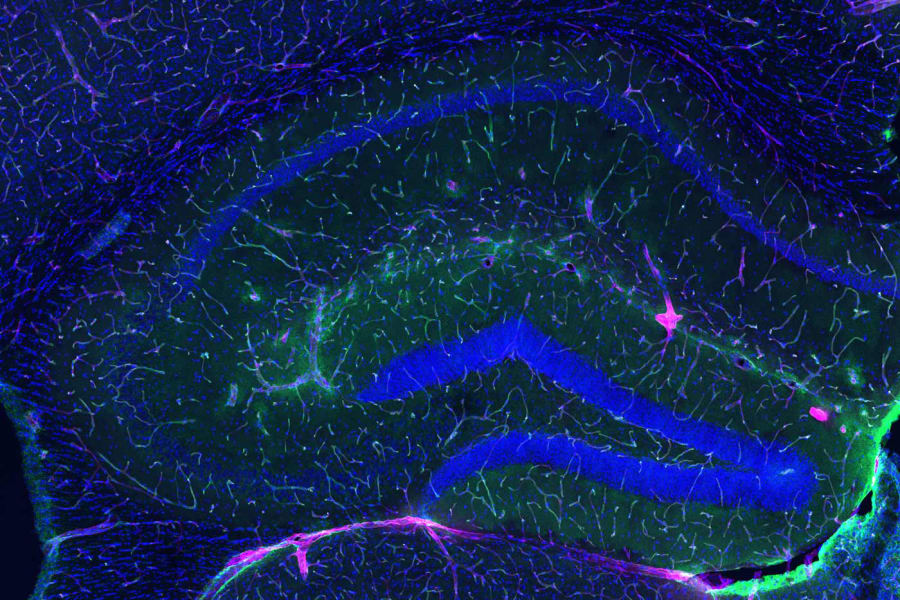

Para comprender la magnitud de este descubrimiento, debemos asomarnos a la microanatomía de la frontera cerebral. La BHE es una interfaz vascular altamente selectiva que separa el cerebro de la circulación sistémica, formada por un mosaico celular inexpugnable: células endoteliales microvasculares cerebrales (BMEC), astrocitos y pericitos.

A diferencia de otros vasos sanguíneos, las BMEC carecen de poros o fenestraciones. Están selladas por uniones estrechas (compuestas por proteínas como claudinas y ocludinas), que restringen severamente el paso de sustancias, permitiendo solo la entrada de nutrientes esenciales y orquestando la expulsión meticulosa de neurotoxinas como el amiloide-beta.

Imagen de portada